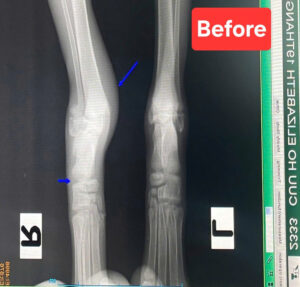

Little Grace had accident. The ankle was wounded and dislocated.

X ray. Replace the bone back to joint. Cast. Treated the infection and inflamation. Strictly care for 21 days.